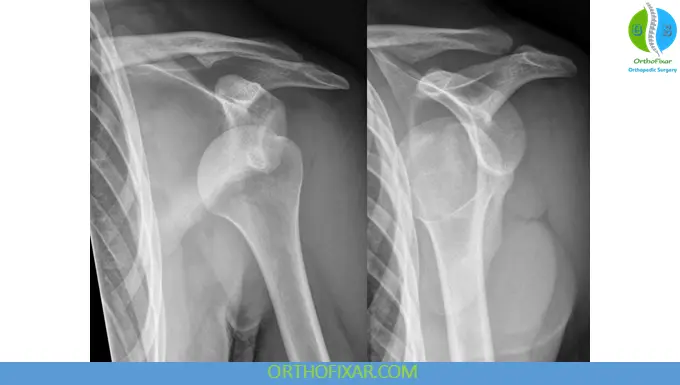

Radiographic Evaluation

Standard Trauma Series

- Anteroposterior (AP) view

- Scapular-Y view

- Axillary view

When to Obtain Pre-reduction X-rays

- First-time dislocation

- Age > 40 years

- High-energy trauma

Alternative View

- Velpeau axillary view

- Used when patient cannot abduct due to pain

Special Imaging Views

- West Point view: evaluates anterior glenoid rim

- Hill-Sachs view: detects posterolateral humeral head defects

- Stryker notch view: identifies humeral head lesions